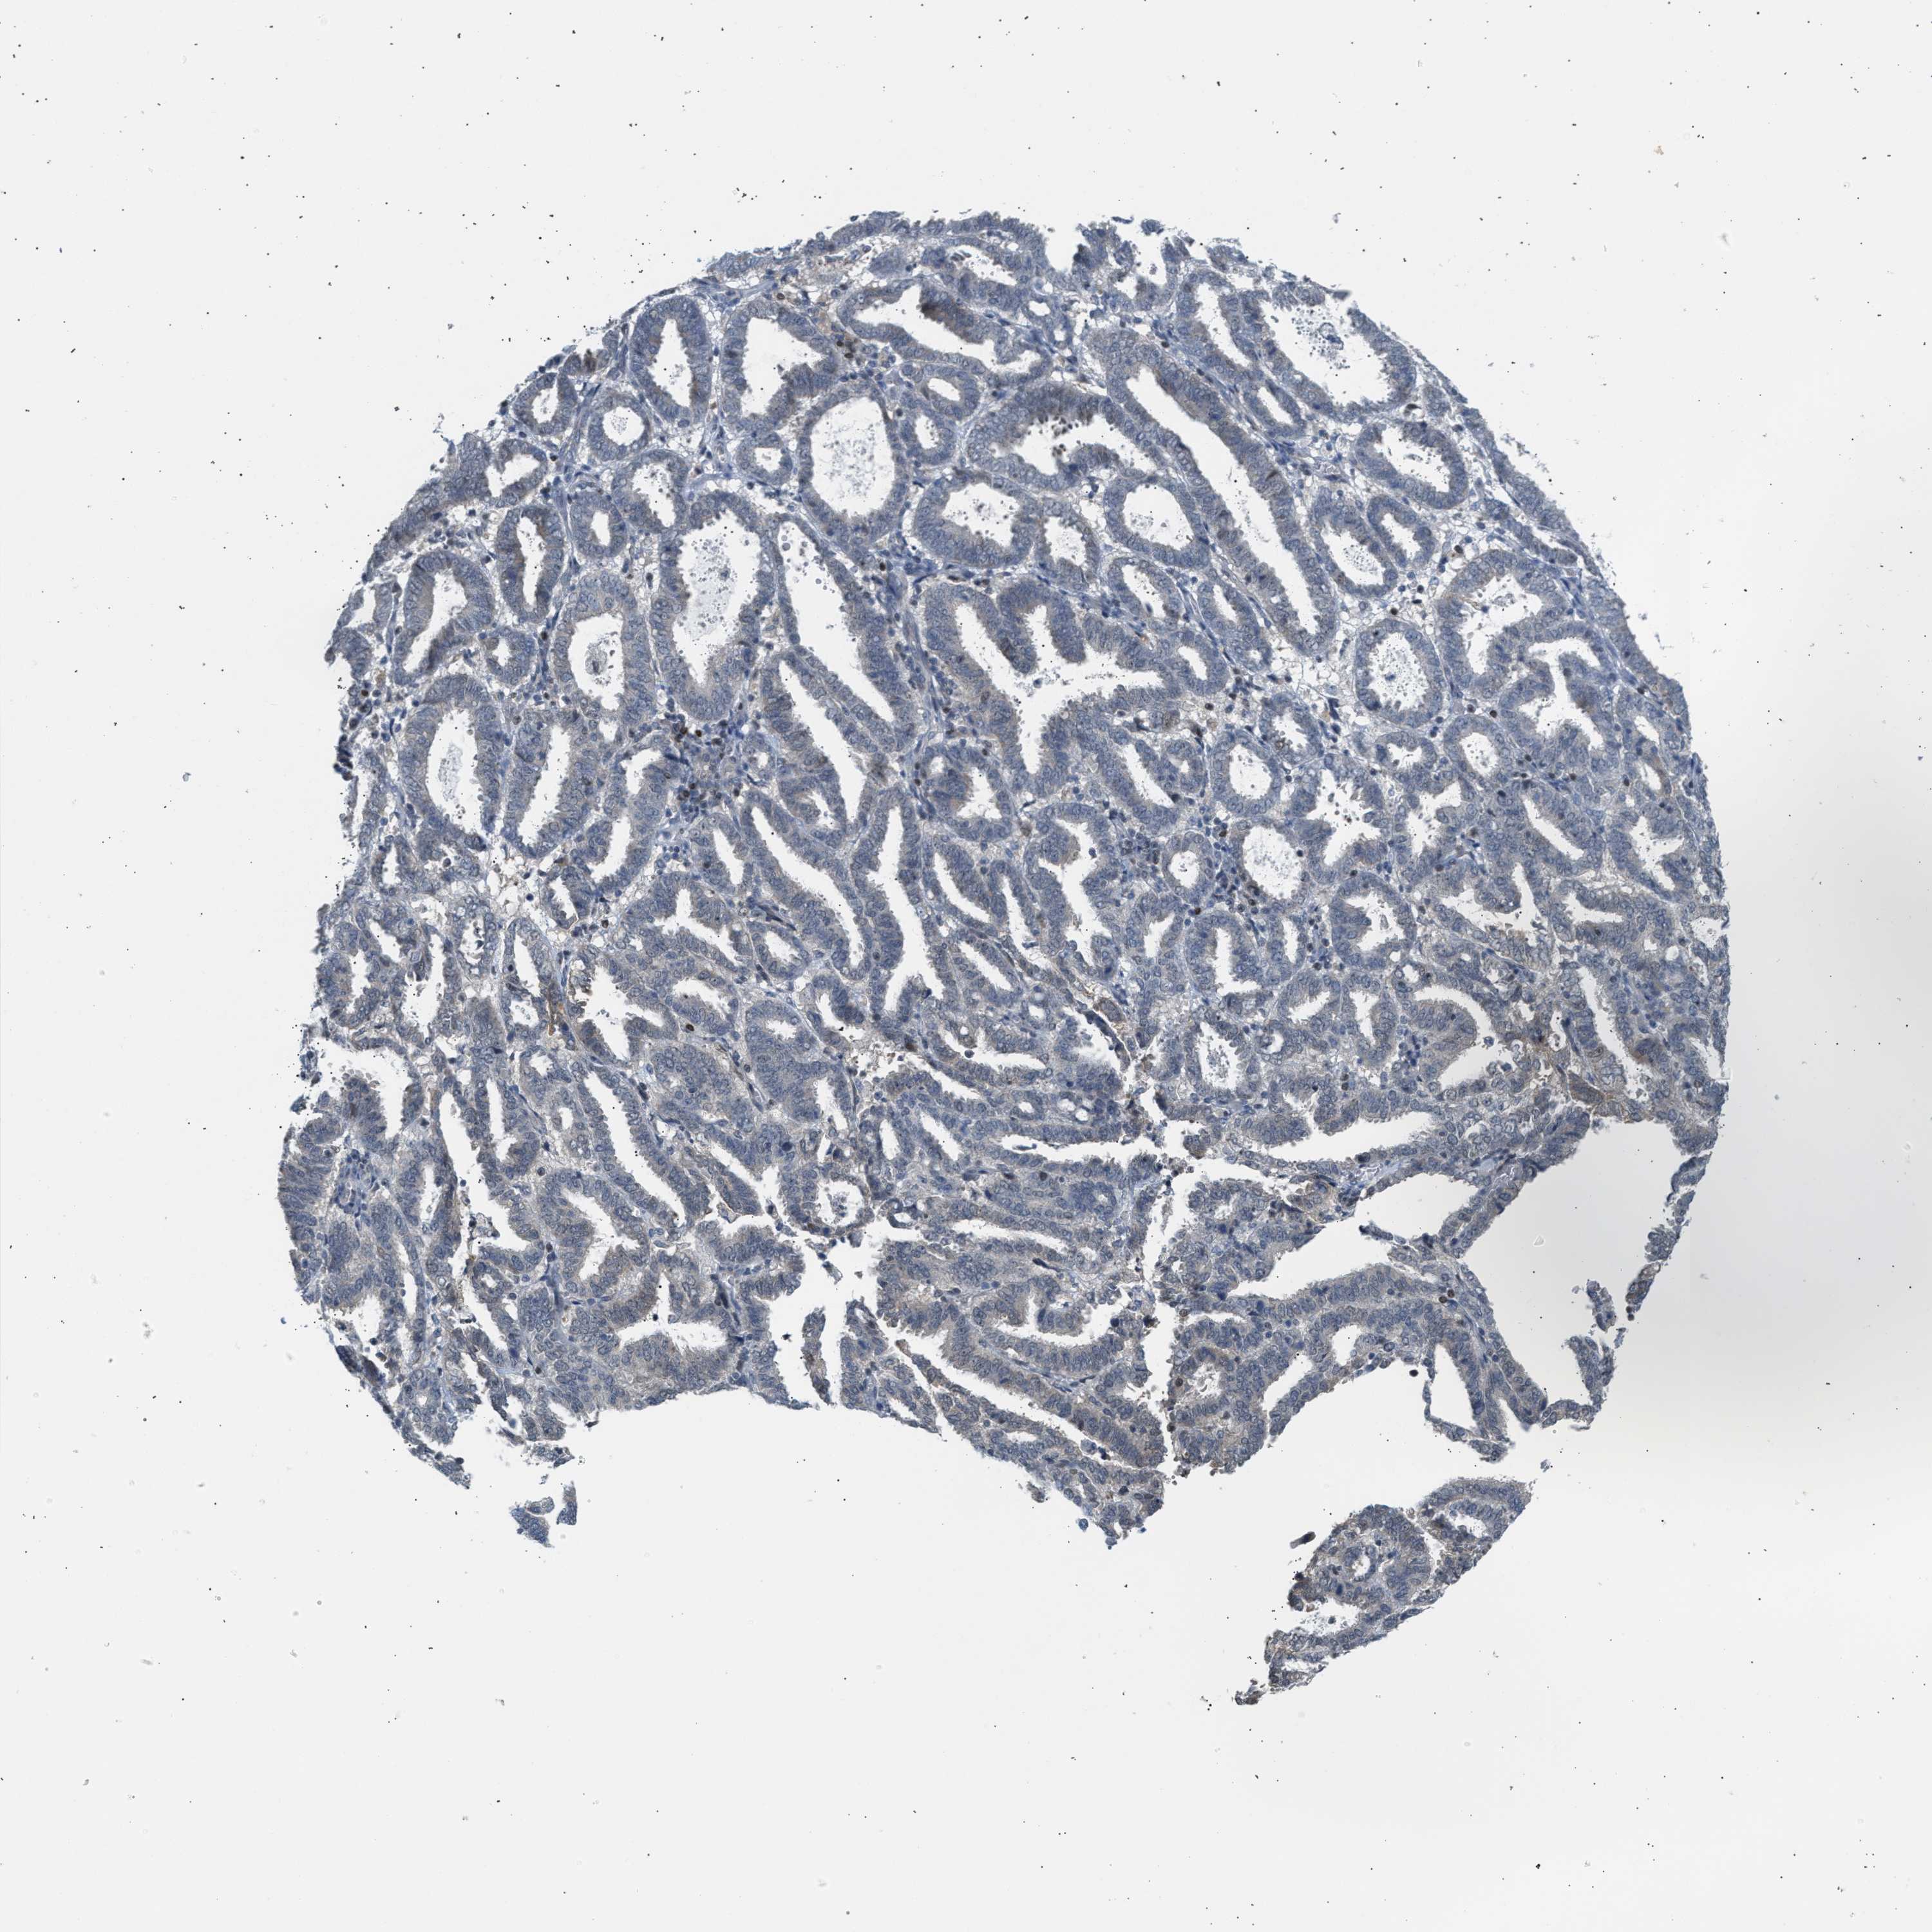

ENDOMETRIAL CANCER - Protein expressioni

A mouse-over function shows sample information and annotation data. Click on an image to view it in a full screen mode. Samples can be filtered based on level of antibody staining by selecting one or several of the following categories: high, medium, low and not detected. The assay and annotation is described here.

Note that samples used for immunohistochemistry by the Human Protein Atlas do not correspond to samples in the TCGA dataset.

Antibody stainingi

Antibody staining in the annotated cell types in the current human tissue is reported as not detected, low, medium, or high, based on conventional immunohistochemistry profiling in selected tissues. This score is based on the combination of the staining intensity and fraction of stained cells.

Each image is clickable and will lead to virtual microscopy that enables deeper exploration of all samples and also displays staining intensity scores, fraction scores and subcellular localization as well as patient and tissue information for each sample.

Antibody CAB020139

Staining

High

Medium

Low

Not detected

Intensity

Strong

Moderate

Weak

Negative

Quantity

>75%

75%-25%

<25%

None

Location

Nuclear

Cytoplasmic/membranous

Cytoplasmic/membranous,nuclear

Adenocarcinoma, NOS